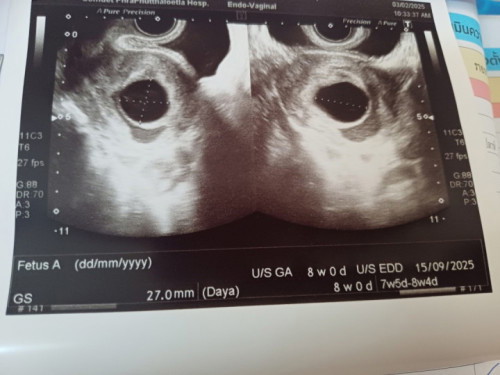

8w+5 อัลตราซาวด์ ไม่พบตัวอ่อน

แม่ๆท่านไหนเคยเจอเหตุการณ์แบบเราบ้างคะ ตอนนี้เครียดทำอะไรไม่ถูกเลย หมอนัดอีกทีสิ้นเดือน แม่ยังพอมีหวังอยู่ไหมคะ😭

หมออัลตราซาวด์ให้แบบไหนคะ แบบสอดช่องคลอดรึป่าวคะ บ้านนี้ไปตรวจตอนแรกก็ไม่เจอค่ะ แต่อัลตราซาวด์ช่องคลอดเจอ 7+1 w ค่ะ แม่อย่าพึ่งกังวลน้าาา

8w 1d ไม่เจอน้องเหมือนกันค่ะ แถมเจอถุงน้ำในรังไข่ด้วย หมอบอกถุงการตั้งครรภ์เล็กยังมองไม่เห็น อีก 2 สัปดาห์ให้ไปซาวด์ดูใหม่อีกทีค่ะ